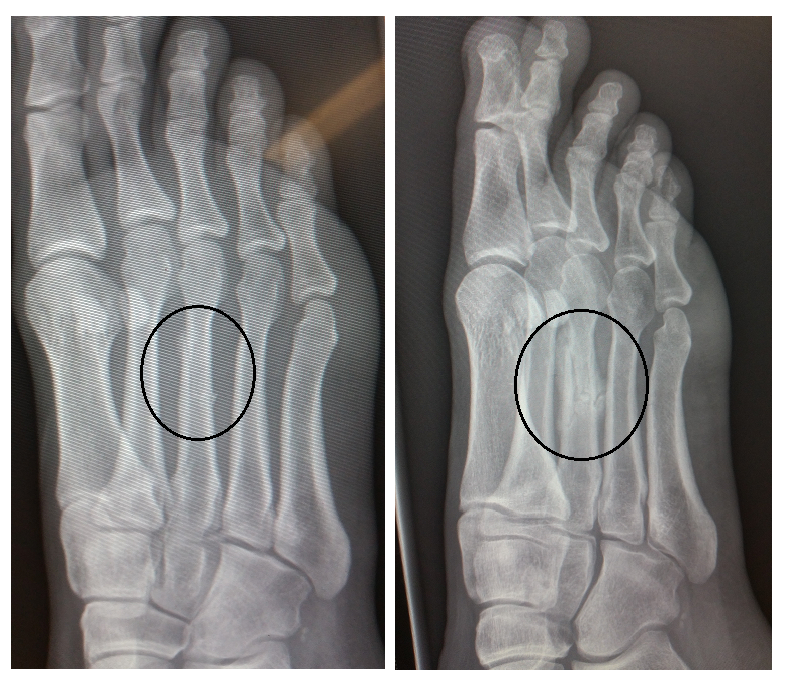

| (Left: Originally fractured foot June 21, 2015, Right: Re-fractured foot August 1, 2015) |

The right side picture shows what the fracture site looks like now. Sure there is evidence of bony callus forming (which means there is lots of healing going on), however, the bones aren't nearly as nicely aligned, and there are a few little "chips" coming off.